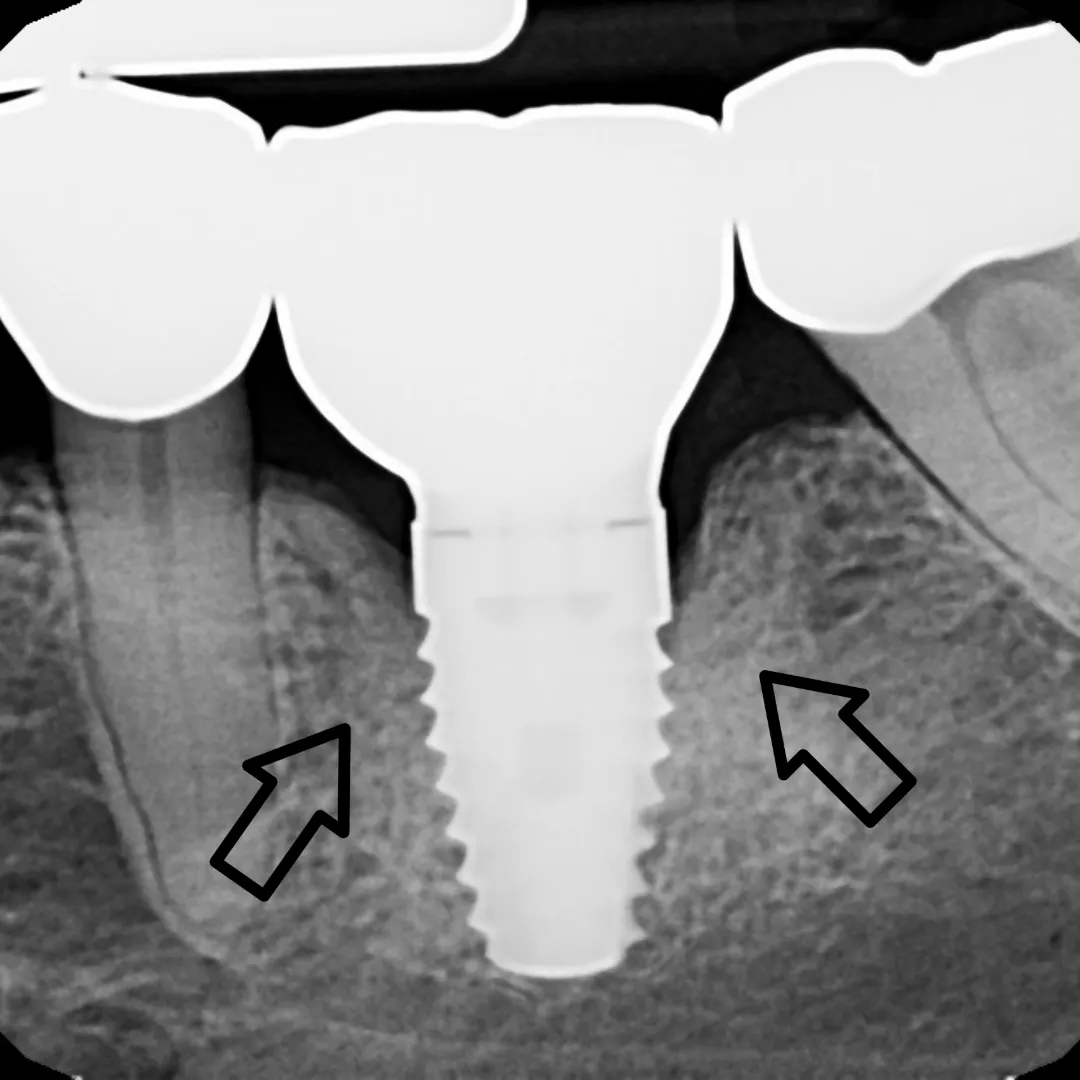

LAPIP

before